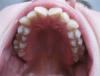

JUl_al Опубликовано 6 апреля, 2011 Поделиться Опубликовано 6 апреля, 2011 Решилась на брекеты, сапфировые (лигатурные). Врач говорит, что необходимо будет удалить 2 зуба сверху и столько же снизу. НО какие пока не знает, потому что снимков я еще ему не показывала. Так что вы первые, господа ортодонты! Врач предполагал удалять не здоровые 4-ки, а 5-ки или даже 6-ку. Интересно еще, как изменится овал лица?Оцените пожалуйста ситуацию. Очень важно ваше мнение. Заранее большое человеческое спасибо! Ссылка на комментарий

guess... Опубликовано 6 апреля, 2011 Поделиться Опубликовано 6 апреля, 2011 врач не направлял вас еще на один снимок? ТРГ-снимок черепа сбоку. а еще хочется челюсти позырить верхнюю и нижнюю Ссылка на комментарий

JUl_al Опубликовано 6 апреля, 2011 Автор Поделиться Опубликовано 6 апреля, 2011 не отправлял пока. Сейчас я жевалки свои выложу, минутку. Пойдет? Ссылка на комментарий